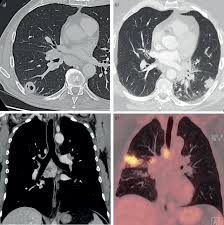

Dermatological Aspects Of Tularaemia A Study Of 168 Cases Polat 2018 Clinical And Experimental Dermatology Wiley Online Library

Dermatological Aspects Of Tularaemia A Study Of 168 Cases Polat 2018 Clinical And Experimental Dermatology Wiley Online Library from onlinelibrary.wiley.com